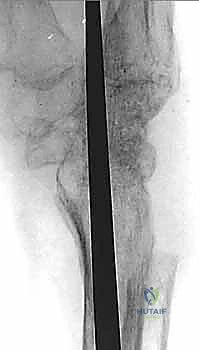

- التصوير بالأشعة السينية (X-rays): الأداة الأساسية لتقييم تضيق المسافة المفصلية (دليل على فقدان الغضروف)، وجود نتوءات عظمية، وتحديد مدى الانهيار في عظام الرسغ.

خطوات العملية الجراحية بالتفصيل: كيف يتم التثبيت؟

تُجرى عملية تثبيت مفصل الرسغ الكلي تحت التخدير العام أو التخدير الموضعي للذراع (Block)، وتستغرق عادة من ساعتين إلى ثلاث ساعات. يتبع الأستاذ الدكتور محمد هطيف الخطوات الدقيقة التالية:

1. الشق الجراحي (The Incision)

يتم إجراء شق جراحي طولي على الوجه الظهري (الخلفي) للرسغ. يقوم الدكتور هطيف بفتح الأنسجة بعناية فائقة، مع الحفاظ على الأوتار الباسطة للأصابع والأعصاب الحسية وإبعادها بلطف عن مجال العمل.